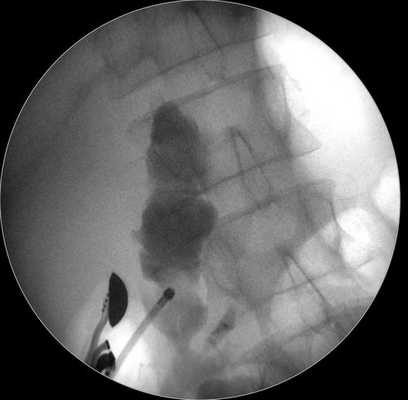

Затем под контролем рентгеноскопии в полость кисты вводится струна-проводник для установки пластикового стента (double pigtail) диаметром 10 Fr и длиной 10 см. Осуществляется рентгенологический и ультразвуковой контроль: он подтвердил, что дистальный конец стента располагается в просвете кисты, проксимальный - в луковице двенадцатиперстной кишки (рис. 5 в, рис. 6). При эндоскопическом осмотре оценивается область сформированного соустья для исключения кровотечения (рис. 7).

Рис. 6